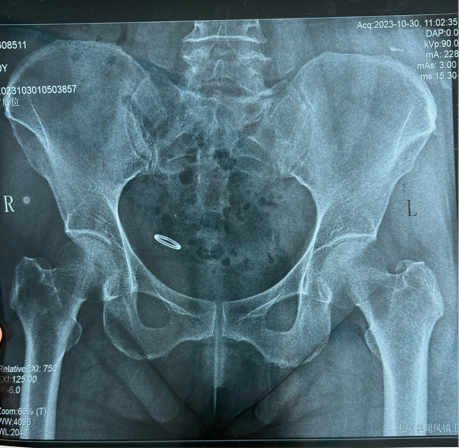

前不久,60岁的钱女士因下腹痛4天来来凤县人民医院就诊,门诊妇科彩超提示宫腔內未见节育器样强回声。行腹部X线提示盆腔内节育器,这可把钱女士吓坏了,这才想起36年前在当地医院上的环还没取呢!

在医生的建议下,钱女士立即办理住院并于第二日行腹腔镜探查术,果然如彩超和X线报告的一样,环形的宫内节育器完全在子宫以外。最终,经过手术成功取出腹腔里的节育器,腹部切口小,术中仅失血约2ml。